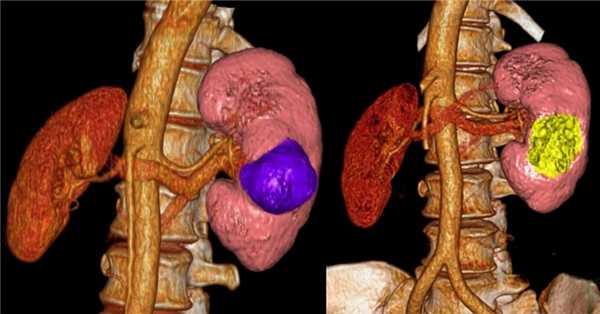

Лимфома почки визуализируется, как множественные слабо контрастируемые образования, но также, как опухоль забрюшинного пространства, прорастающая в почки и/или мягкие ткани, окружающие почки.

На изображении двустороннее поражение почек и поражение костей у пациента с В-клеточной лимфомой.

Вот еще один пациент с лимфомой, локализированной в средостении, поджелудочной железе (стрелка) и в обеих почках.